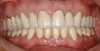

Figure  1  Natural tooth wear.

Figure 1

Dental structure is a mineralized tissue that undergoes a dynamic process of remineralization and demineralization in the oral cavity. In the presence of supersaturated and normal functioning saliva, calcium and phosphate ions leach from the dental structures. These are then taken up in the presence of fluoride, thus maintaining a homeostasis. In response to chemical challenges and mechanical adversities, such as erosion, abrasion, attrition, and abfraction, the irreversible loss of mineral components from dental tissue occurs (Figure 1).